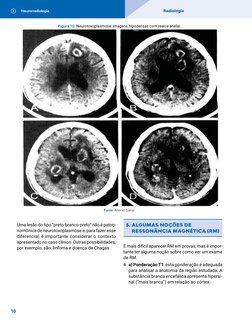

Figura 10. Neurotoxoplasmose: imagens hipodensas com realce anelar.

Fonte: Acervo Sanar.

Uma lesão do tipo “preto-branco-preto” não é patog- 5. A LGUMAS NOÇÕES DE

nomônica de neurotoxoplasmose e, para fazer esse RESSONÂNCIA MAGNÉTICA (RM)

diferencial, é importante considerar o contexto

apresentado no caso clínico. Outras possibilidades,

por exemplo, são: linfoma e doença de Chagas. É mais difícil aparecer RM em provas, mas é impor-